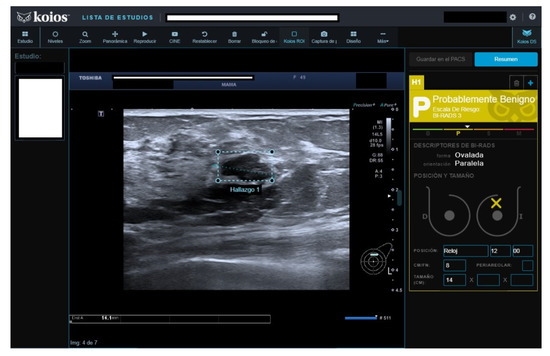

Figure 4.

Nodule rated B3 by reader (no Doppler), KSS by KOIOS. Cytology reported grade 1 carcinoma. Biopsy confirmed invasive carcinoma.